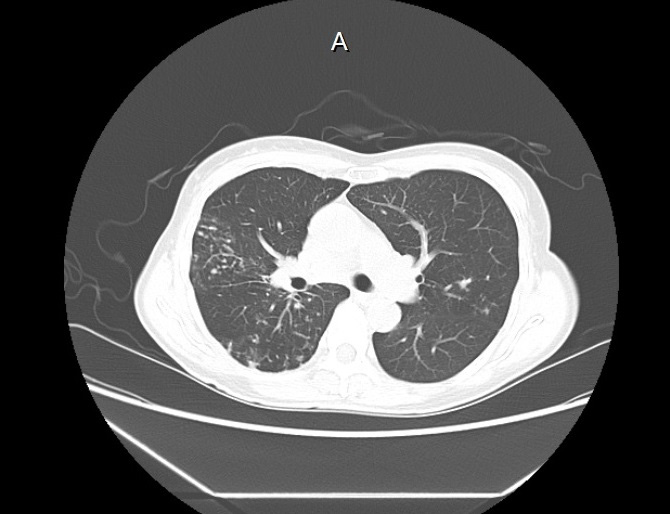

기관지확장증의 CT 사진